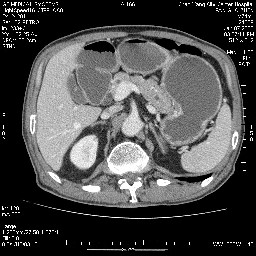

女,74岁,呕吐10余日

肝胰壶腹占位,考虑-壶腹癌!

胃体部粘膜不规则增厚,胃肠造影也显示充盈缺损-胃溃疡?胃癌?

壶腹部占位;考虑:壶腹癌!源于胰腺可能。

病变主要位于钩突(癌)。如是壶腹部,肝内外胆管扩张明显。

十二指肠降段扩张,水平段狭窄成鼠尾状,肠壁明显增厚,胰腺勾突增大成不均匀强化,其内可见低密度区,胆囊增大,1十二指肠水平段腺癌侵犯胰腺勾突可能大,2胰腺癌侵犯十二指肠(只有胆囊增大没有肝内外胆管扩张不好解释)代除外.

上消化道造影见十二指肠结节状充盈缺损,ct增强十二指肠壁局限性增厚并强化,考虑十二指肠壶腹癌?

十二指肠降段扩张,水平段狭窄成鼠尾状,肠壁明显增厚,胰腺勾突增大成不均匀强化,其内可见低密度区,胆囊增大,1十二指肠水平段腺癌侵犯胰腺勾突可能大,2胰腺癌侵犯十二指肠 。

今日手术结果:胰腺钩突癌侵犯十二直肠,腹腔淋巴结转移.